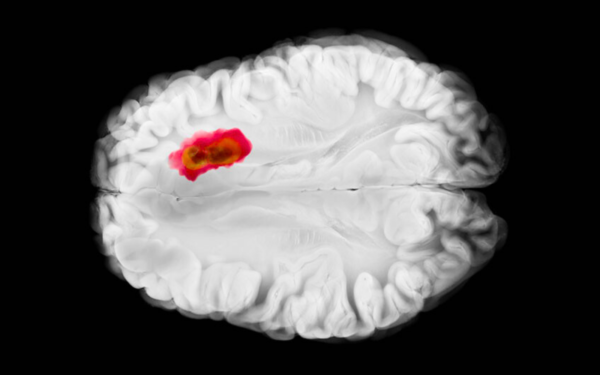

Breakthrough in the surgical treatment of glioblastoma

Doctors at a hospital in Łódź have performed Poland’s first surgery to remove a glioblastoma using PET imaging with 18-fluorotyrosine, a technique currently used in only a few neurosurgical centers worldwide. Additional patients are now being sought who could undergo this innovative therapy.